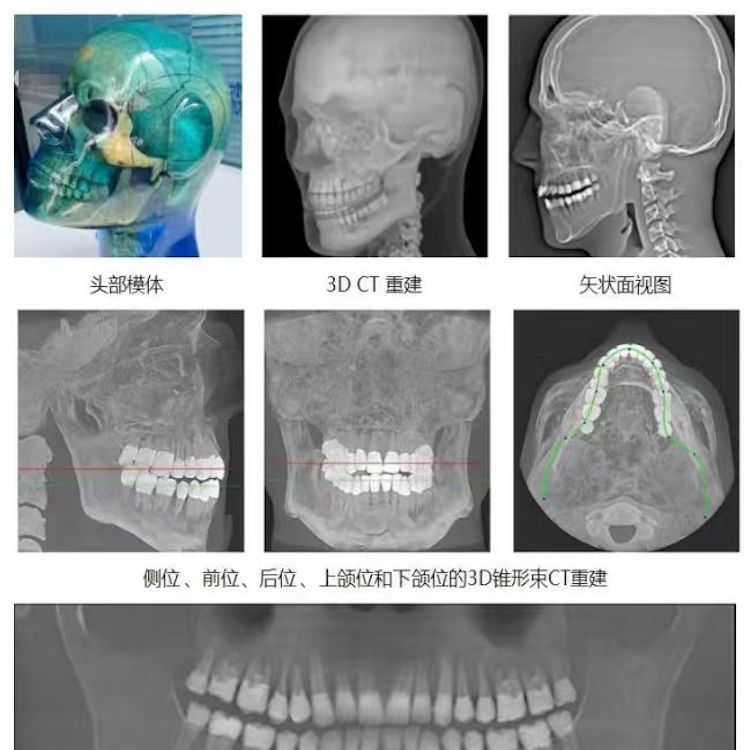

頭部模體是頭部診斷放射學的參考標準,該模體旨在協助技術和臨床人員,在大多數需要精細解剖細節(jié)的放射學程序中選擇、監(jiān)測、培訓和驗證掃描參數。 模體為研究人員、臨床醫(yī)生和技術人員提供了一致性的工具。它非常適合確定最佳系統設置、調試新設備、監(jiān)測系統性能和培訓牙科X射線、全景X射線、CT和錐束CT程序。 這個模體包括一個可調節(jié)的支架,用于在錐束 CT 或全景X射線系統中定位。模體的下頜略微張開,前牙垂直排列,以復制正確的咬合引導定位 。 請注意,實際咬合引導無法在這個產品中定位。 頭部模體是由專有組織等效材料制成的。由組織模擬樹脂制成,這些樹脂模擬X射線對人體的衰減特性,適用于CT和治療能量范圍(50keV-25MeV)。 模體在大小和結構上都近似于平均男性頭部 。該模體包括詳細的3D擬人化解剖結構, 包括大腦、骨骼、喉、氣管、鼻竇、鼻腔和牙齒。骨骼包括皮質和骨小梁的分離。牙齒包括明顯的牙本質、牙釉質和包括神經的牙根結構。鼻竇完全張開。

頭部模體特點 1. 詳細的解剖特征; 2. 確定法蘭克福平面以確保正確對齊; 3. 50 keV 至 25 Mev 的組織等效值; 4. 具有六個自由度的定位支架; 5. 包括泡沫內襯手提箱; 6. 12個月保修。

功能和應用 1. X射線 ,全景X射線 ,CT和錐束CT系統; 2. 學習如何正確定位頭部以獲得最佳圖像; 3. 測試重建技術和算法 ,用于植入物規(guī)劃和頜面部重建; 4. 在實施新設備和新技術期間培訓并評估人員; 5. 驗證圖像質量的一致性。